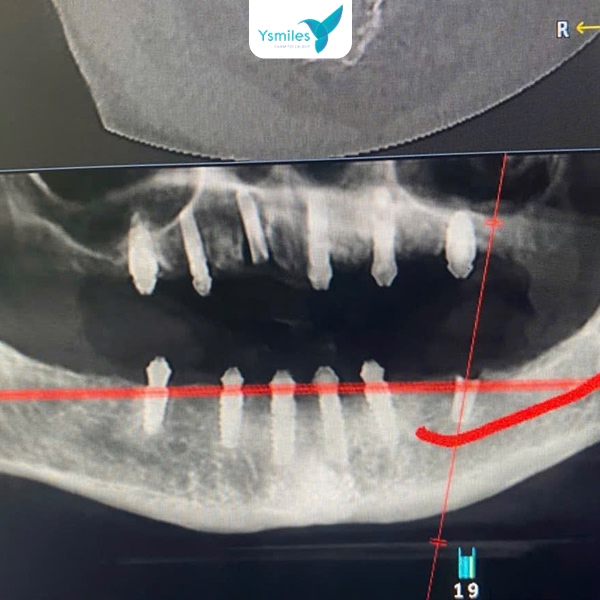

- Trang thiết bị công nghệ hiện đại: Việc áp dụng công nghệ hiện đại giúp ca trồng răng Implant diễn ra chính xác, an toàn và nhanh chóng hơn, kéo theo chi phí có thể cao hơn so với các cơ sở kém đầu tư về máy móc.

Chụp X-quang kiểm tra vị trí trụ Implant của răng

- Trang thiết bị hiện đại: Ysmiles liên tục cập nhật công nghệ chẩn đoán và điều trị chuẩn quốc tế, áp dụng công nghệ vào quy trình trồng răng Implant giúp đảm bảo tính chính xác và an toàn tuyệt đối.